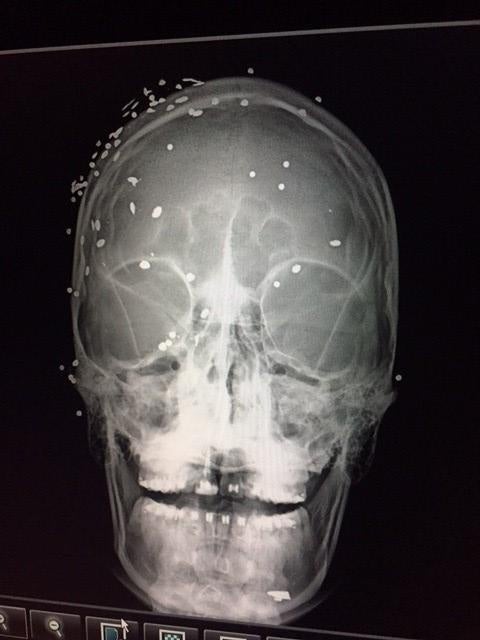

Security agents have also denied or failed to provide access to medical treatment to some detainees who had preexisting medical conditions or suffered serious injuries during their arrest and subsequent detention—including being shot with pellets at very close range.